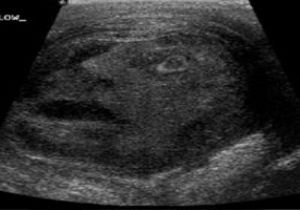

45 yaşındaki bir erkek hastanın ultrason görüntüsü hastane çalışanlarını ve gören herkesi şaşkınlığa uğrattı.

Kanada'da yaşayan ve ismi açıklanmayan erkek hastanın ultrason görüntüsünde ortaya çıkan gözlerini ve ağzını açmış, korku içinde bakan bir yüz silueti ortaya çıktı.

Testislerinde tümör olduğu anlaşılan erkek hastanın tümörü daha sonra operasyonla alındı ve tümörün iyi huylu olduğu anlaşıldı.